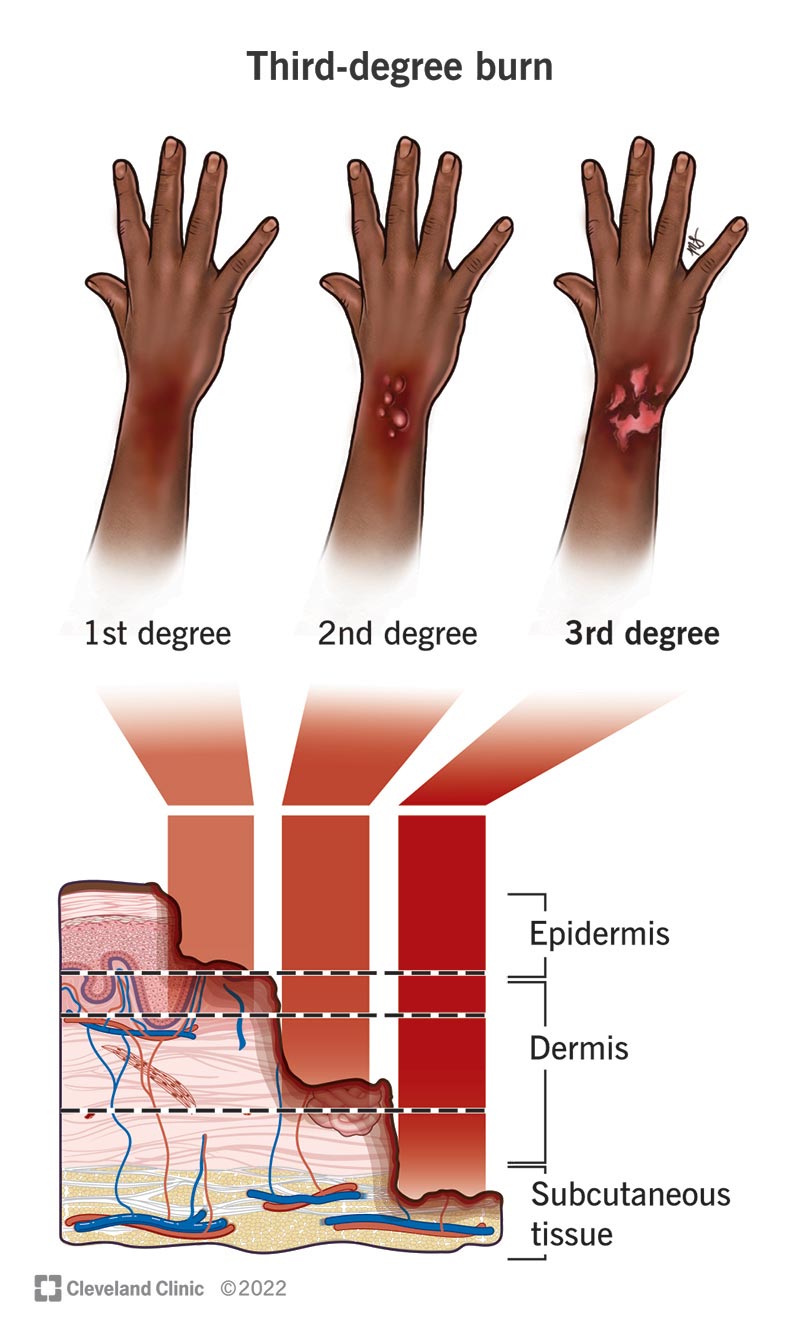

Burns First Aid Guide

Leathery Skin After Burn

Medical Vector Illustration Burn Stages Degree Burns Of Skin 8910124

Leathery Skin After Burn

3 Astme P letus Mis See On Ravi Ja Paranemine SFOMC